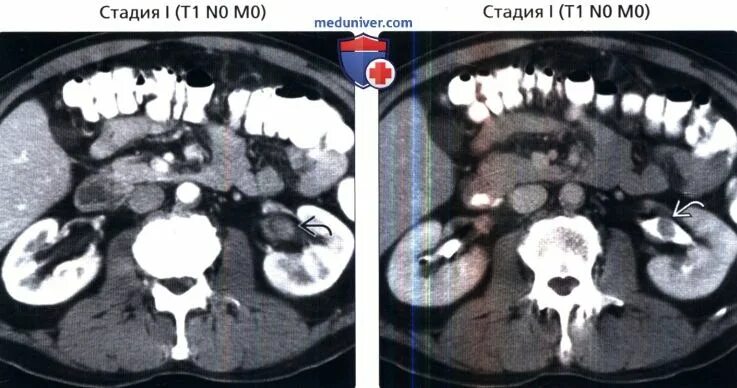

Могут ли метастазы перепутать